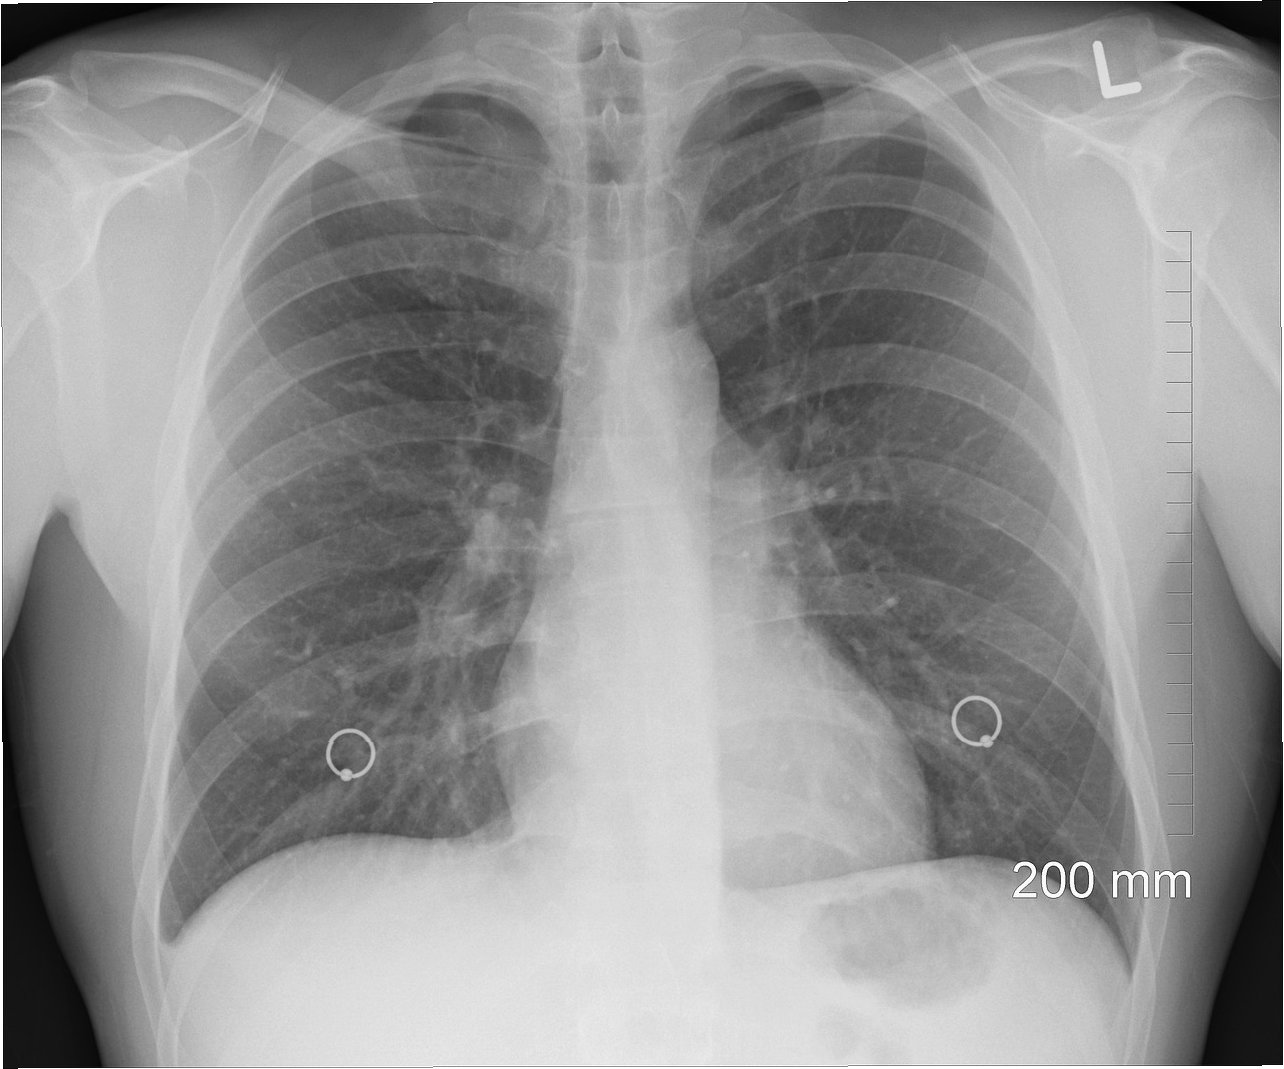

한의사의 엑스레이(X-ray) 사용을 가능하게 하는 법안을 두고 의사와 한의사 사이의 갈등이 격화하고 있습니다. 의사단체는 "한의사의 엑스레이 사용은 과학적 검증과 전문성이 없어 위험하다"며 거세게 반발하는 반면, 한의사들은 "시대착오적인 직역 이기주의"라며 맞서고 있습니다.

한의사의 엑스레이 사용을 허용하는 의료법 개정안은 진단용 방사선 발생장치의 안전관리책임자에 대한 규정을 바꾸는 내용이 골자입니다. 현행 의료법은 의료기관 개설자 등이 방사선 장치를 설치할 경우 보건복지부령에 따라 안전관리책임자를 선임하도록 하고 있으며, 안전관리책임자의 자격은 의사, 치과의사, 방사선사 등으로 제한하고 있습니다.

이에 대해 의협은 "국민 건강과 생명을 혼란에 빠뜨리는 치명적인 도발"이라고 일갈했습니다. 김택우 의협 회장은 "의료법에 따라 한의사는 한방 의료행위만 할 수 있고, 한의사의 엑스레이 사용은 명백히 무면허 의료행위에 해당한다"며 "엑스레이는 고도의 전문성과 해부학적 지식이 있어야 하는 의료장비인 데다 방사선 차폐시설과 영상의학과 기사 등을 확보해야 한다"고 지적했습니다.